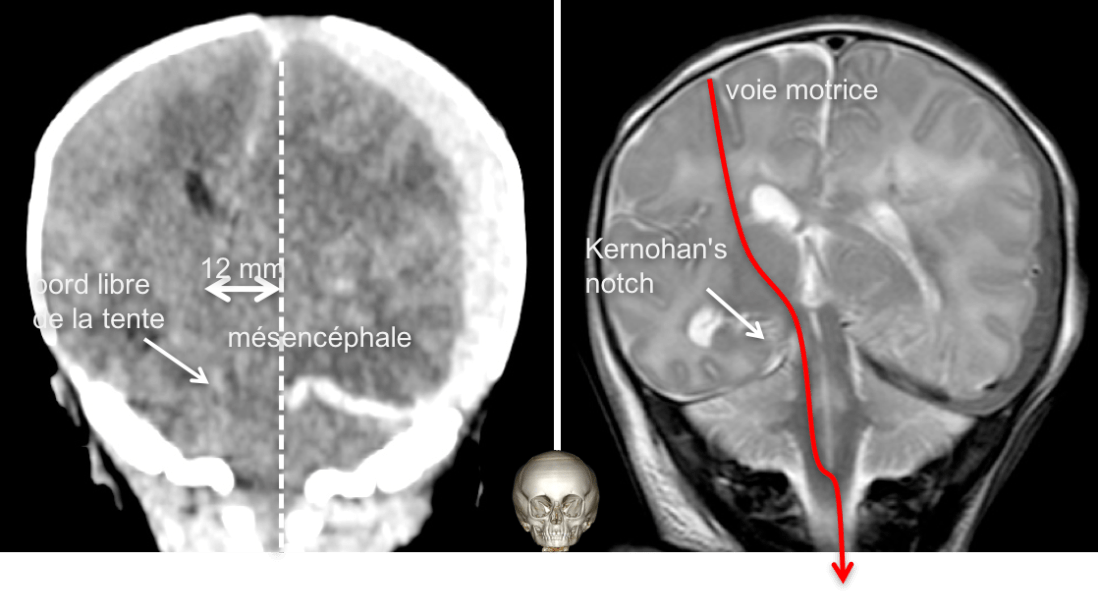

l’engagement sous-falcoriel

il traduit une compression importante avec ischémie par compression de l’artère péricalleuse homolatérale, voire bilatérale, contre le bord libre de la faux du cerveau.

dans les hématome sous-duraux, le rapport entre la surface à la convexité et celle à l’intérieur du bord libre de la faux est à l’origine d’un un levier multiplicateur de l’engagement.

cliniquement, il s’agit d’un tableau d’HTIC sévère qui n’a pas de caractère spécifique mais qui comporte un risque important de séquelles neuropsychologiques (lésions frontales bilatérales).

l’engagement paradoxal

appelé Kernohan’s notch, du nom de l’anatomo-pathologiste qui l’a décrit, il survient lorsqu’un facteur compressif (le plus souvent un hématome sous-dural) exerce une pression homogène sur l’encéphale, entraînant un déplacement avec compression du mésencéphale du côté opposé contre le bord libre de la tente du cervelet

il provoque donc une paralysie homolatérale à la compression (d’où le paradoxe).